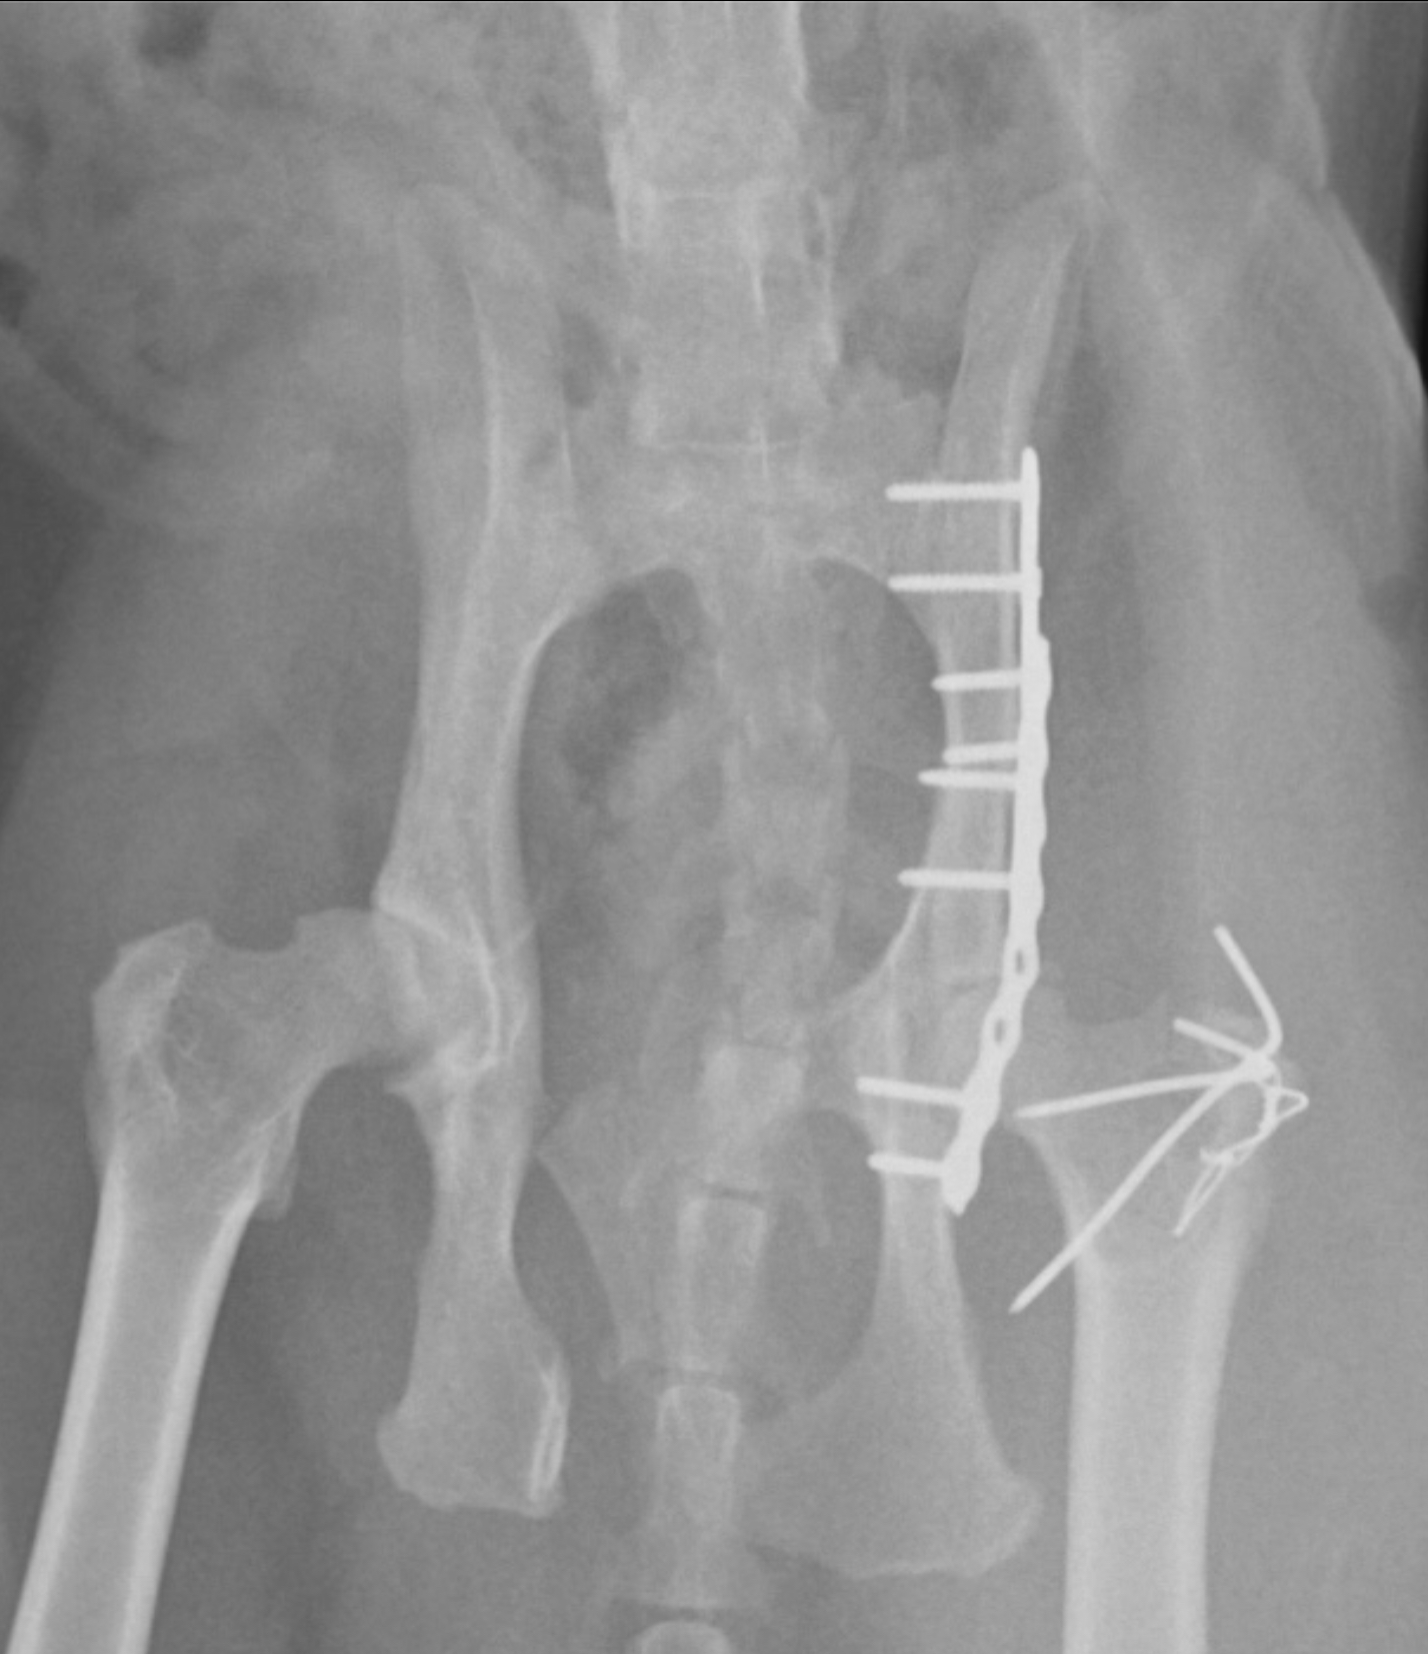

骨折による激しい疼痛と、歩行困難の治療、骨盤狭窄による排便困難を予防するため、手術を行いました。

左腸骨の骨折に対して、プレート法を実施しています。(ロッキングプレートを2枚使用)

手術後のレントゲン写真